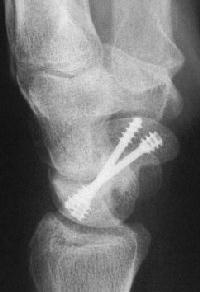

Case 8. Transscaphoid perilunate fracture dislocation...

Click for larger image

Two screws put in dorsally, LT ligament reinforced with a strip of extensor retinaculum left attached to the triquetrium and anchored into the lunate; temporary capitolunate pin.